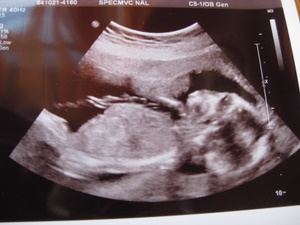

Ahogy ígértem, hoztam a képeket. Igaz Ti idősebbek vagytok a képeken, mert Boti a képeken 14+6 hetes, Ti meg ugye már 17+3 :)

Dodó Pocaklakó Kép

Boti

Kép

Dodó Pocaklakó

Na mazsolázzunk... :D